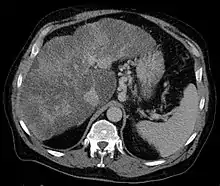

Isolated gastric varices of Sarin classification IGV-1 seen on gastroscopy in a patient with portal hypertension | |